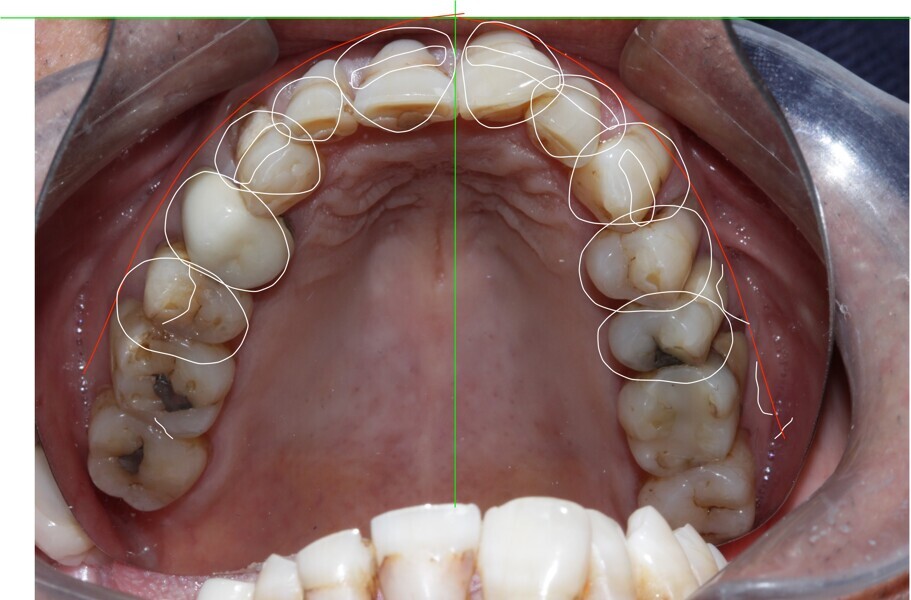

Figure 10 Digital smile desinging planning

Figure 11 Digital smile designing planning